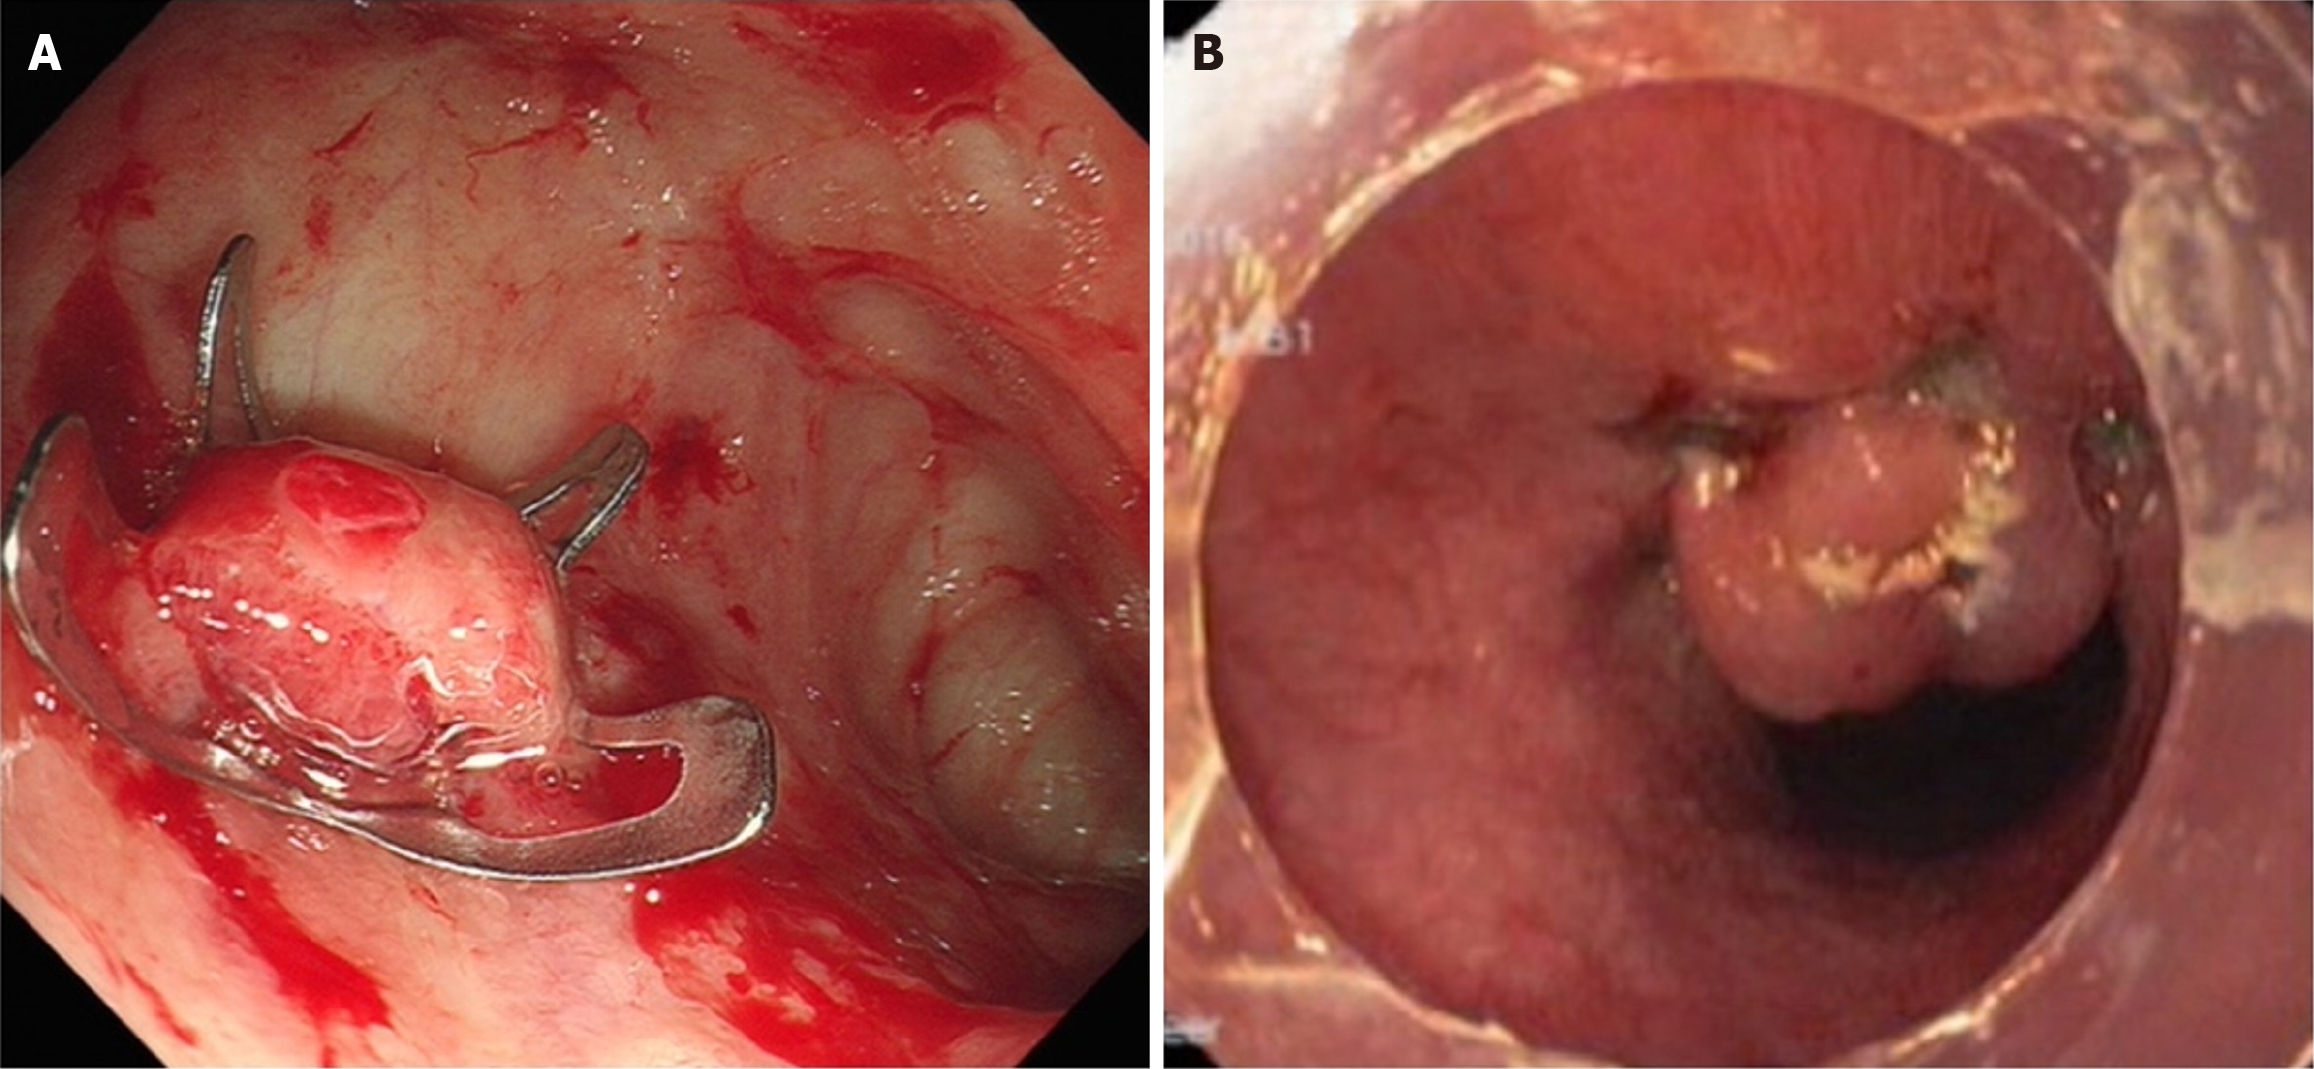

OTSCs are used when durable, broad tissue capture is needed e.g., fibrotic edges, large defects, or tangential locations and for hemostasis, full-thickness apposition, and device anchoring (Padlock/Ovesco)[56,65]. Evidence from randomized trials and meta-analyses supports first-line use in selected high-risk NVUGIB, with lower early rebleeding and higher clinical success vs standard endoscopic therapy[18,56,66,67,69]. Beyond hemostasis, OTSCs are effective for acute iatrogenic perforations, post-surgical or anastomotic leaks, and fistulas (e.g., gastrocutaneous, colorectal), where near full-thickness apposition improves sealing and durability[71-73]. Additional uses include post-EMR/ESD defect closure - especially in thin-walled locations such as the duodenum - and stent fixation to prevent migration when clinically indicated[37,65] (Figure 5).

Figure 5

Figure 5 Deployed over-the-scope clip. A: An Ovesco clip was used for hemostasis of a bleeding duodenal ulcer with pulsatile vessel; B: A Padlock clip was deployed to close a tracheoesophageal fistula after application of argon plasma coagulation on the edges[73]. Citation for Figure 5B: Rai P, Bhargava R. Successful closure of post-tracheostomy large chronic tracheoesophageal fistula with new over-the-scope clip. Dig Endosc 2017; 29: 634. Copyright© The Authors 2025. Published by Wiley. The author obtained permission from the publisher and was approved (Supplementary material).